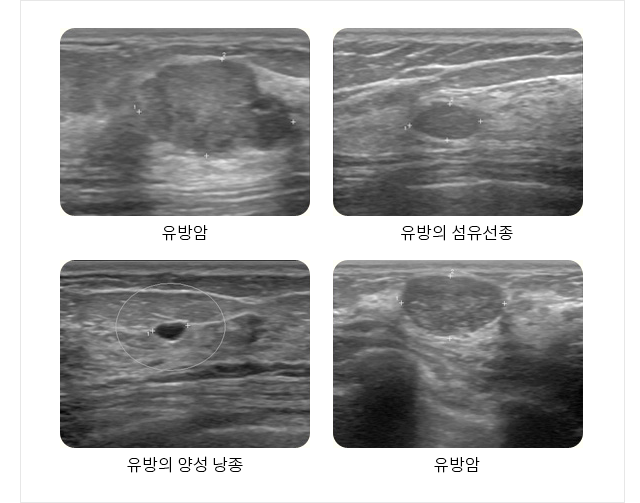

복부 초음파, 간섬유화 검사 갑상선, 유방 초음파 경동맥 초음파 관절 초음파